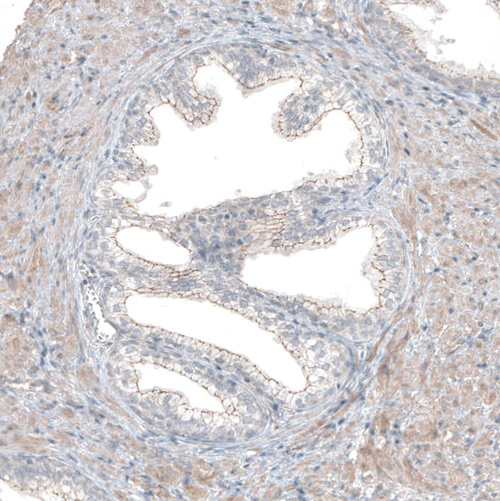

Immunohistochemical staining of human endometrium shows moderate membranous positivity in glandular cells.